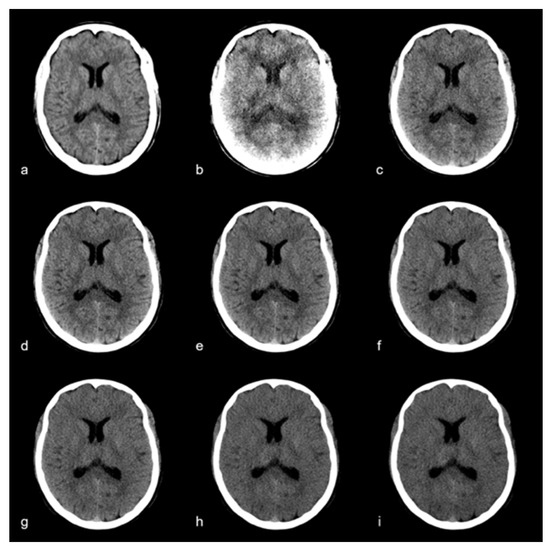

2.3. Quantitative Image Analysis